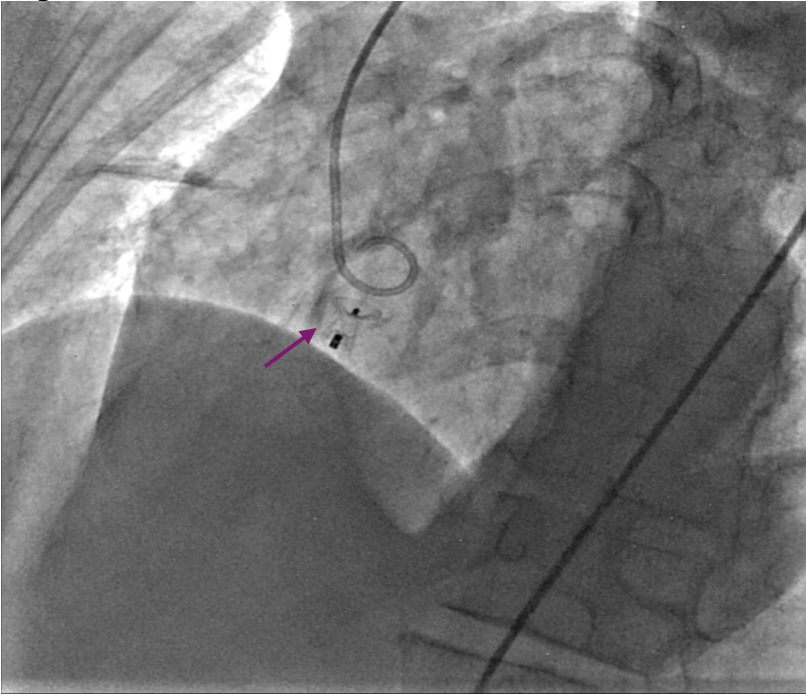

Ultrasound-guided dual access was completed, with a right femoral arterial as well as a venous approach. An aortogram was performed using the arterial approach, following introduction of a pigtail catheter at the level of the non-coronary aortic sinus, which showed a connection between the right atrium and the non-coronary aortic sinus (Figure 1, Video 1).

Figure 1. An aortogram revealing a communication between the right atrium and the non-coronary sinus of Valsalva (white arrow).

Figure 5. (A) Device deployed (purple arrow). (B) Transthoracic echocardiography.